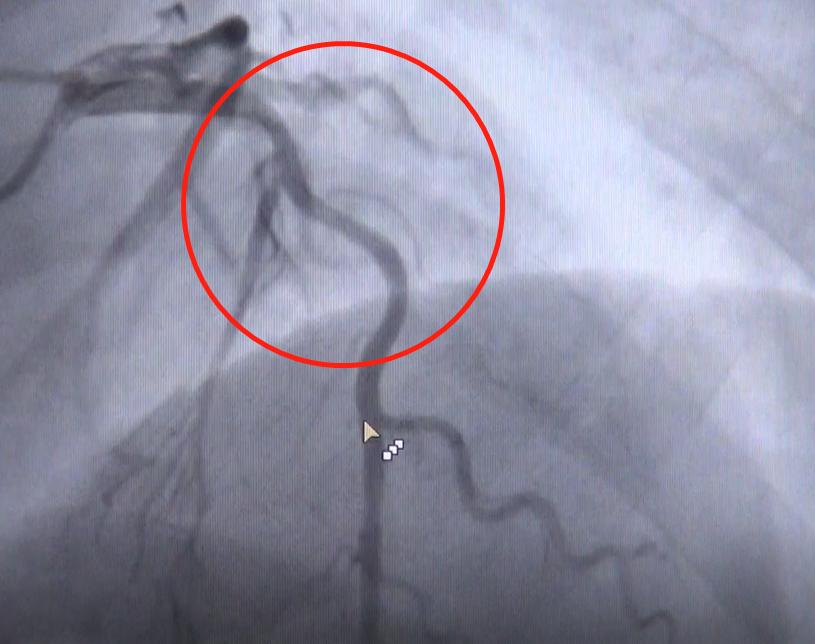

造影的结果,如同他4月份在老家医院一样:前降支的近中段位置,预估大概狭窄50~60%,确实不明显。后来医生打了硝甘,把血管尽量扩开之后,评估出最大狭窄程度,也只70%这个水平。

不过,按照生理结构特点推断,冠脉血管应该是由粗逐渐变细,越来越细的生理结构。而老宋的血管,好像上下一样粗,中间部分猛然间收缩了。

医生判断,这支血管病变范围是比较广的,比较弥漫均匀,所以才会造成看着还可以的错觉。